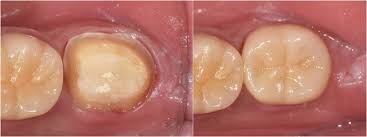

치과 치료 절차

- X‑ray 및 육안 진단 → 상태 확인

- 재접착 가능 시 임시/영구 접착 → 안 되면 새 크라운 제작

- 임시 크라운 장착 후 최종 크라운 장착 (1~2주 소요)